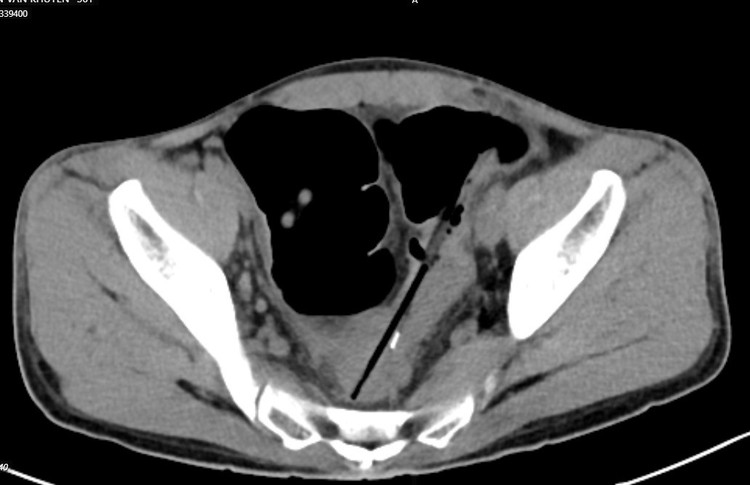

Chụp cắt lớp ổ bụng thấy hình ảnh 02 dị vật hình que đầu kim loại trong quai ruột vùng hạ vị, đâm xuyên thành ruột tạo ổ dịch khí vùng tiểu khung cạnh cơ bịt phải; Dị vật trong quai ruột hạ sườn phải; Dày thành trực tràng, đại tràng sigma và quai ruột ngang rốn; Giãn lan tỏa các quai ruột non.